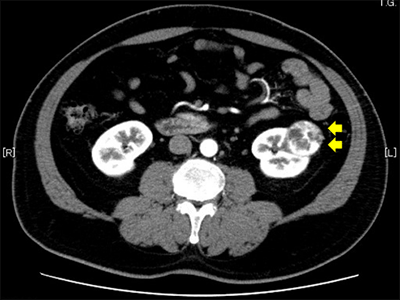

副腎がんは進行性であることが多く、急速に広がります。これは、副腎が最も重要な臓器の1つであるためです。

体内における副腎の位置により、副腎腫瘍は症状を引き起こす前に大きく成長する可能性があります。副腎がんが通常、初期段階では発見されず、診断時までに他の領域に転移していることが多いのはこのためです。

副腎がんが転移する最も一般的な領域は近くのリンパ節、次に肝臓や肺などの臓器です。